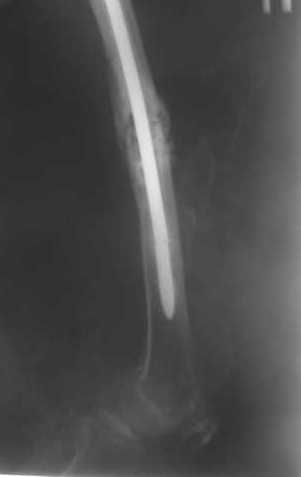

Пациенту М., 30-ти лет, 1,5 года назад в одной из московских больниц был выполнен остеосинтез бедренной кости штифтом UFN (диаметр штифта 9 мм).

К нам больной поступил с признаками ложного сустава бедренной кости, перелома

штифта и дистального блокирующего винта (images 1,2,3).